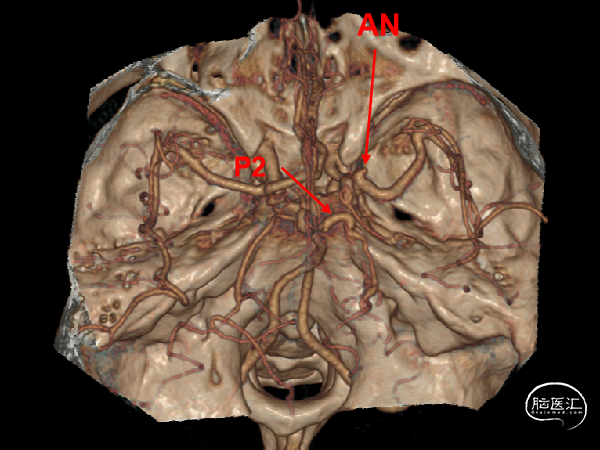

DSA:右侧P1段一6.8*9.7mm不规则囊状突起动脉瘤,远端P2段呈螺旋状蛇形动脉瘤改变。

DSA:右侧P1段一6.8*9.7mm不规则囊状突起动脉瘤,右侧A1段动脉瘤。夹层蛇形动脉瘤。

椎动脉压颈3D

1.颅内多发动脉瘤

右侧P1-P2段夹层动脉瘤

右侧A1段动脉瘤